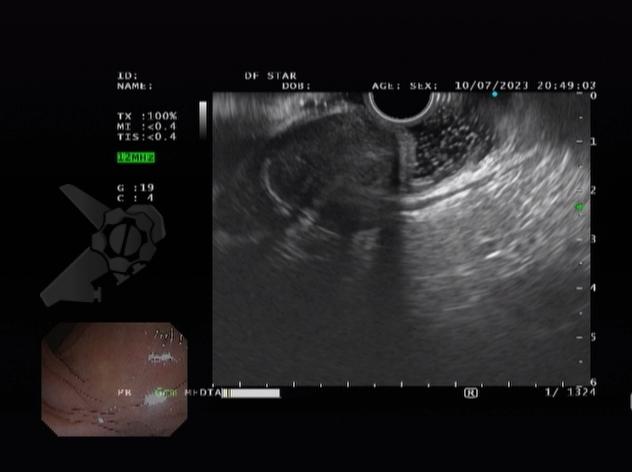

L.R.S., masculino, 8 meses, nascido a termo, com diagnóstico pré-natal de atresia de esôfago com fístula traqueoesofágica distal (Vogt IIIb/Gross C), submetido à correção cirúrgica no 3º dia de vida. Aos 3 meses, passou a apresentar episódios recorrentes de tosse durante a alimentação, engasgos, regurgitação e perda de peso progressiva. A mãe relatou dificuldade em introduzir alimentos sólidos e episódios recorrentes de infecção respiratória nos últimos dois meses. Solicitada endoscopia digestiva alta, que evidenciou estenose puntiforme da anastomose esofágica. Iniciada terapia endoscópica com dilatação esofágica utilizando vela de Savary-Gilliard. Foram realizadas 4 sessões com intervalo de 2 semanas, com melhora progressiva da aceitação alimentar e ganho ponderal adequado. Após a 4ª dilatação, o paciente encontra-se em boa evolução clínica, com alimentação por via oral plena, sem episódios de engasgos ou perda ponderal.

O diagnóstico deve ser suspeitado diante de sinais e sintomas como perda ponderal, disfagia, engasgos e infecções respiratórias recorrentes, vindo a ser confirmado através da endoscopia digestiva alta [11].